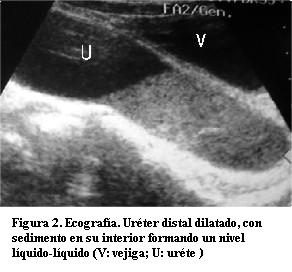

Se solicitó una ecografía abdominal que mostró el riñón izquierdo aumentado de tamaño, a expensas de una severa dilatación pielocalicial midiendo la pelvis renal 50 mm en sentido antero posterior; el espesor del parénquima mide 3 mm, sin diferenciación córticomedular. Uréter homolateral dilatado, tortuoso, de 30 mm de calibre en toda su extensión; en el sector pelviano su interior contiene nivel líquido-líquido, con material heterogéneo, ecogénico en su porción declive. No se logra visualizar la entrada del uréter en la vejiga. Riñón derecho sin alteraciones topográficas, morfológicas ni ecoestructurales. Vejiga sin alteraciones parietales ni del contenido. No se observa líquido libre en la cavidad peritoneal. Resto de la ecografía abdóminopelviana sin alteraciones. En suma: cuadro clínico imagenológico compatible con uréterohidronefrosis infectada (figuras 1 y 2).